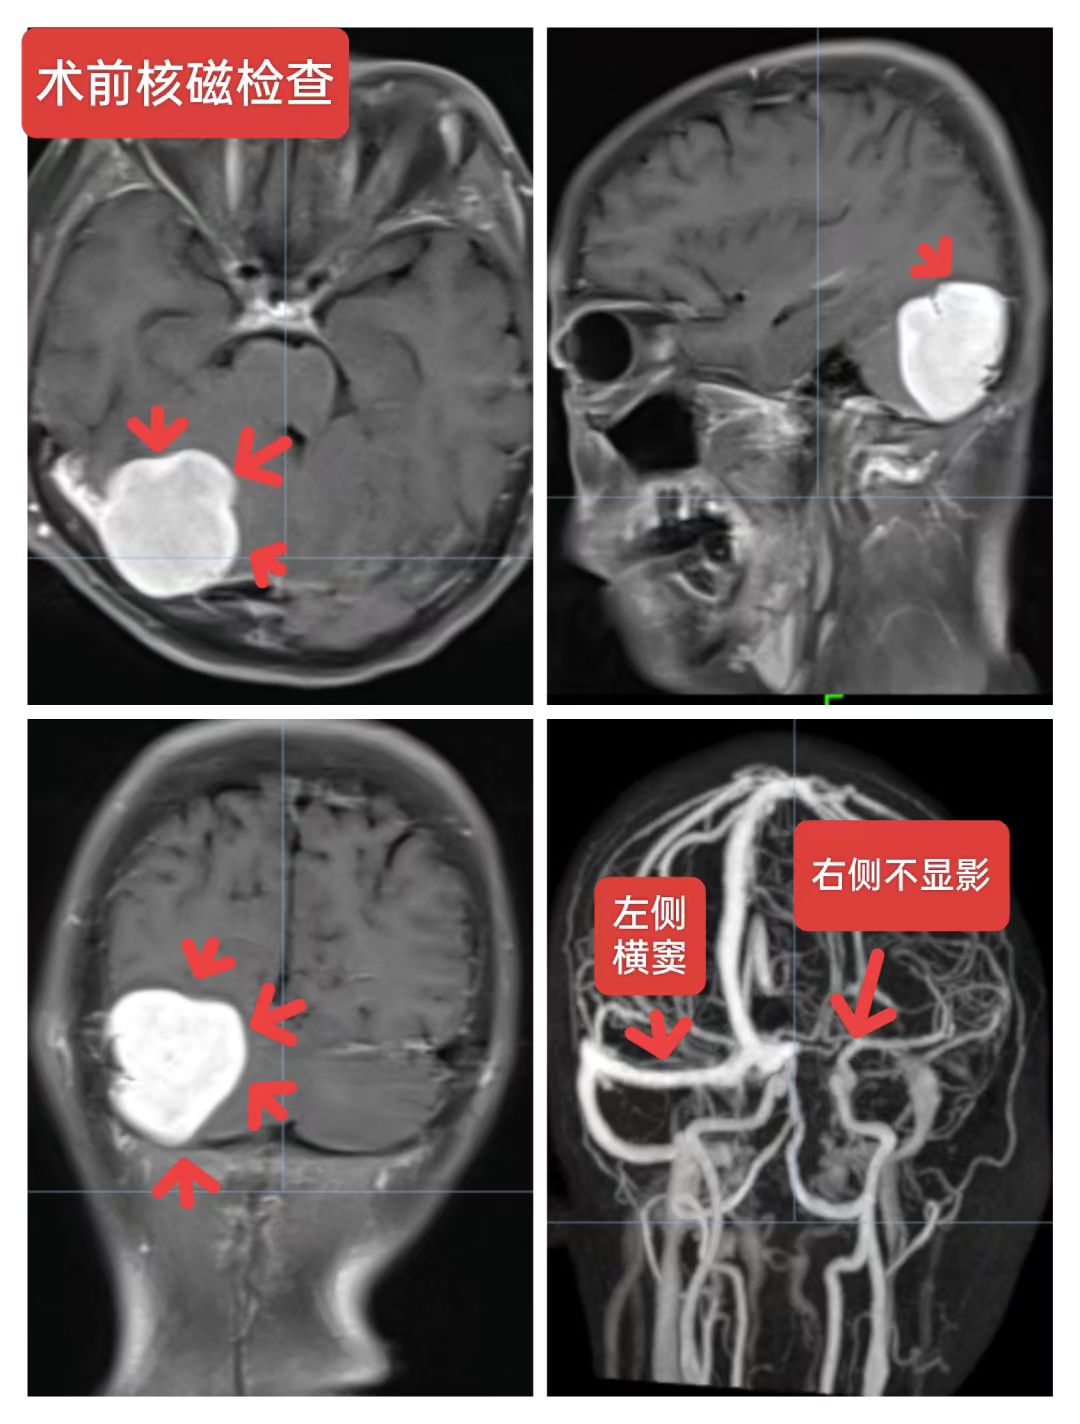

右侧小脑半球脑膜瘤:患者56岁女性,间断性头痛一年,加重一周入院,头颅核磁提示:右侧小脑半球脑膜瘤,压迫横窦,侵蚀天幕向幕上生长,术中见肿瘤质地韧,肿瘤突破硬脑膜,局部骨质破坏,横窦壁有侵蚀,窦壁少量残留,侵蚀硬脑膜及肿瘤全切除,取人工硬脑膜修补缝合,目前患者恢复良好。